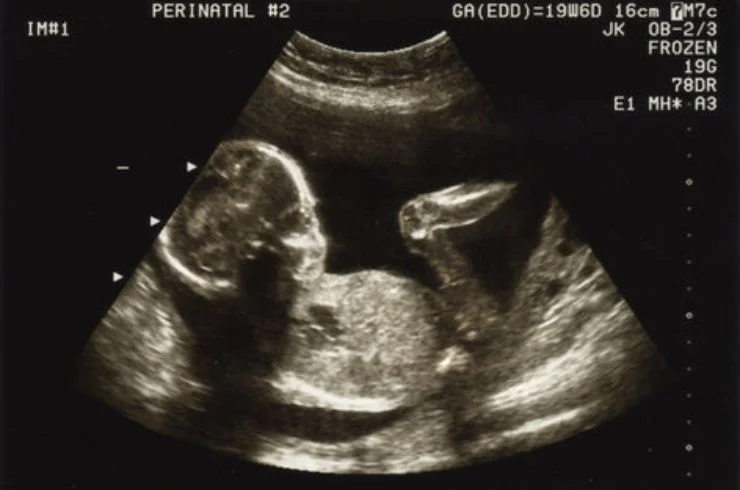

A specialized fetal scan to assess baby's growth and detect abnormalities, ensuring comprehensive prenatal care.